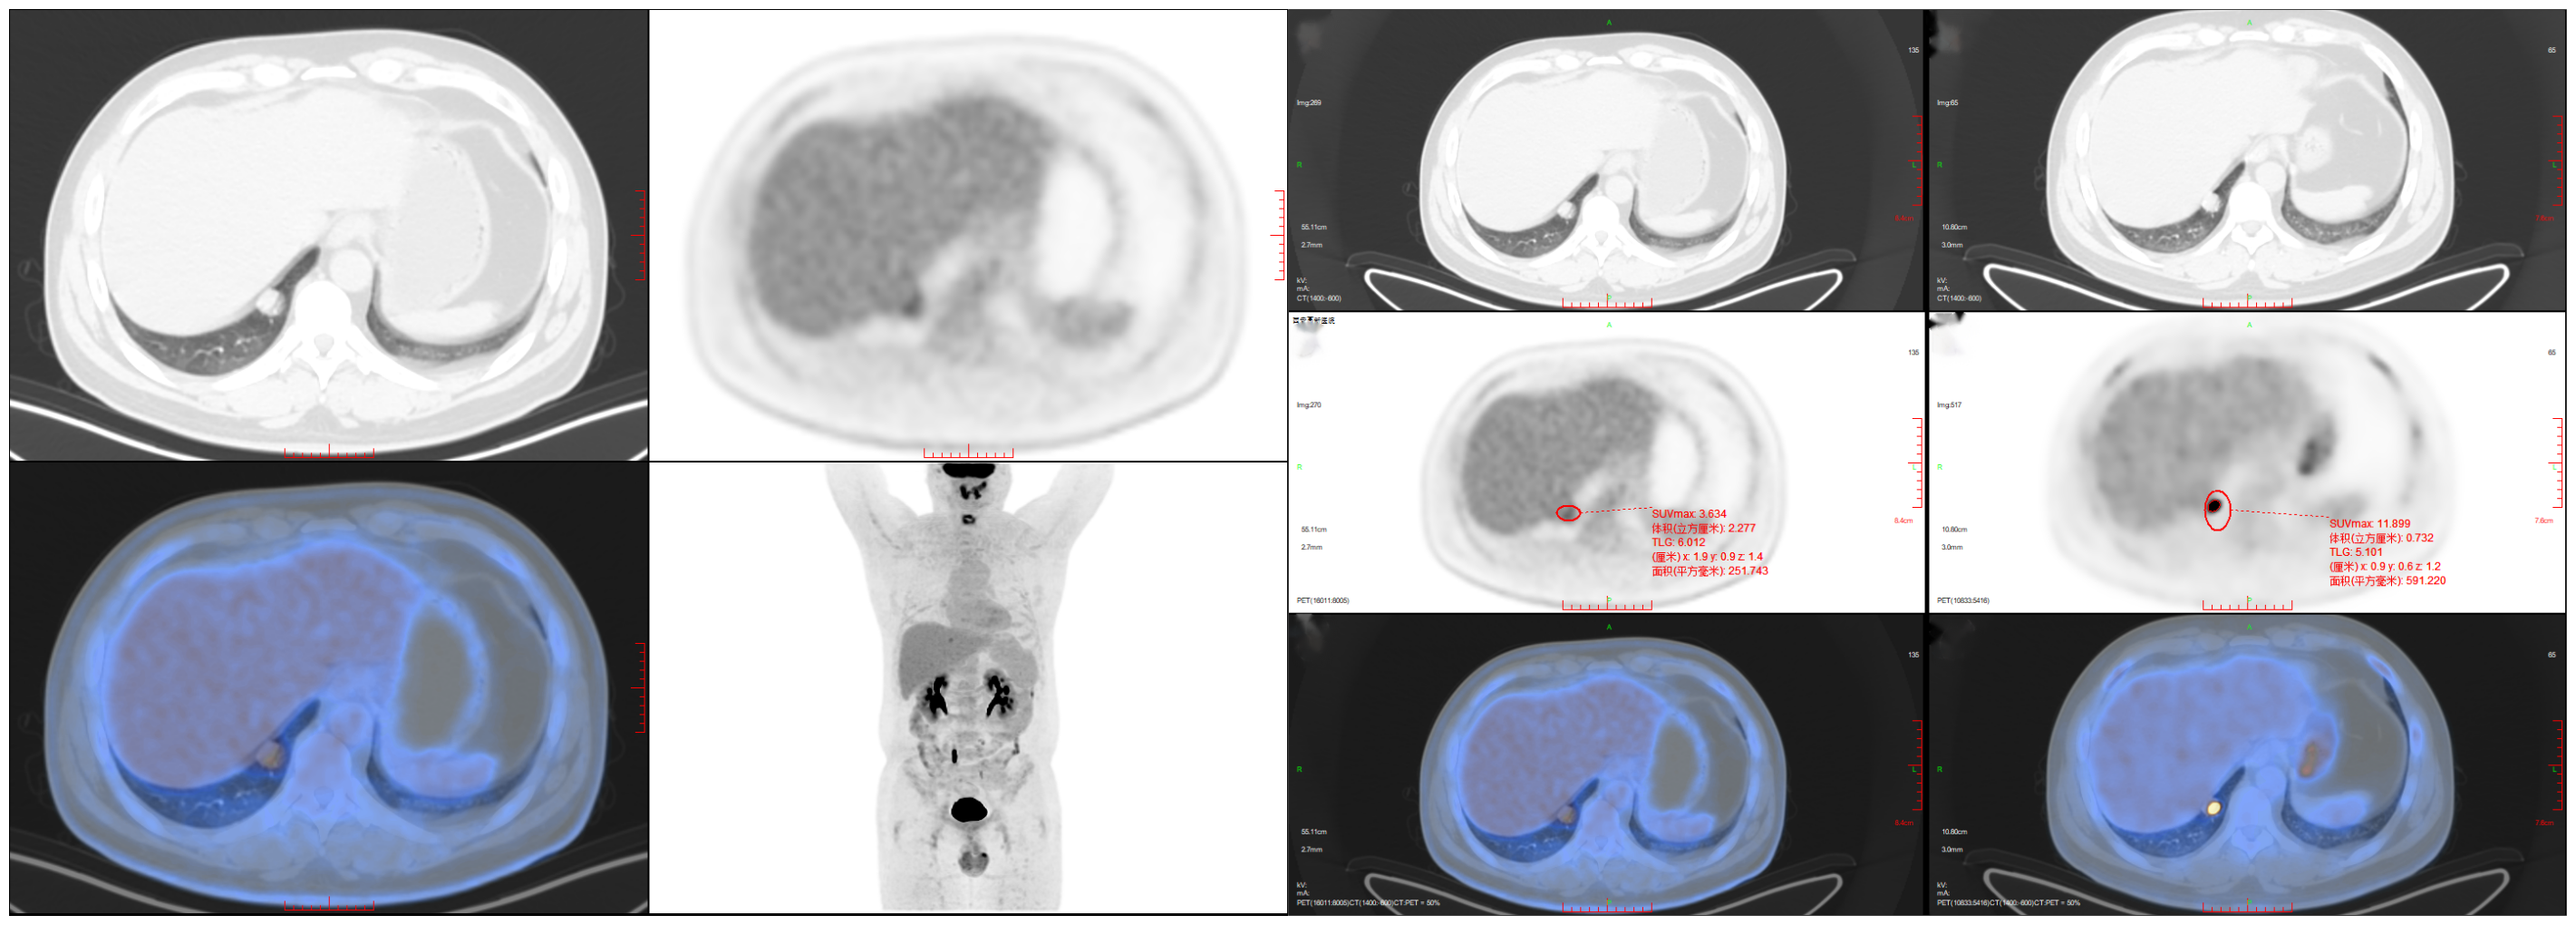

患者男性,體檢胸部CT發(fā)現(xiàn)右肺下葉實性結(jié)節(jié)影,性質(zhì)待定。PET/CT見雙肺紋理分布正常,右肺下葉內(nèi)基底段(IM255)見實性結(jié)節(jié)影,大小約17mm?14mm,可見分葉、胸膜凹陷征象,早期核素呈結(jié)節(jié)狀異常高攝取SUVmax3.63,延遲掃描核素異常高攝取SUVmax11.89;考慮右肺下葉肺癌。